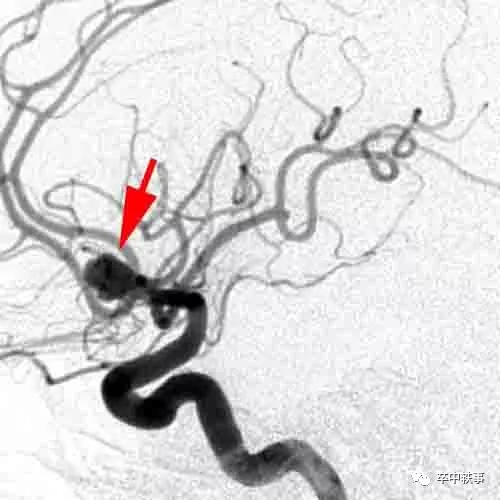

从1990年起人们可以介入栓塞颅内动脉瘤了 (上图)。开刀夹闭动脉瘤手术越来越少了。

现在想看见颅内动脉瘤变得容易多了,各种检测技术都开展了。我还是喜欢坐在 DSA 室内,看型状千奇百怪的颅内动脉瘤。